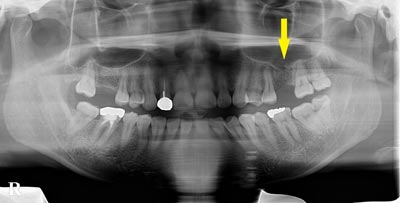

この患者様は、上顎の右前歯が差し歯になっていたのですが、歯の根の先の部分が、腫れを繰り返し、歯根の破折も考えられるとのことで、抜歯して、インプラントかブリッジかと説明されたそうで、インプラント治療を希望されて、当院に相談に来られました。

この患者様は、上顎の右前歯が差し歯になっていたのですが、歯の根の先の部分が、腫れを繰り返し、歯根の破折も考えられるとのことで、抜歯して、インプラントかブリッジかと説明されたそうで、インプラント治療を希望されて、当院に相談に来られました。

CTでみると、歯の根の外側の薄い骨がなく、ここに炎症を起こすと、症状の改善は難しい状態でした。抜歯してインプラントということで了承され、抜歯即時インプラント埋入も考えられたのですが、歯の根の状態、骨の状態を考えて、抜歯して、治癒を待ってインプラント埋入をすることとしました。

CTでみると、歯の根の外側の薄い骨がなく、ここに炎症を起こすと、症状の改善は難しい状態でした。抜歯してインプラントということで了承され、抜歯即時インプラント埋入も考えられたのですが、歯の根の状態、骨の状態を考えて、抜歯して、治癒を待ってインプラント埋入をすることとしました。

抜歯して5か月経過後にCT撮影すると、非常に良く治癒していましたが、骨の厚みが4mm程しかありませんでした。そこで、インプラント埋入と同時に外側に人工骨と自家骨を混合して補填し、人工の膜(メンブレン)で覆うという、骨の厚みを造成する手術(GBR)を併用しました。

抜歯して5か月経過後にCT撮影すると、非常に良く治癒していましたが、骨の厚みが4mm程しかありませんでした。そこで、インプラント埋入と同時に外側に人工骨と自家骨を混合して補填し、人工の膜(メンブレン)で覆うという、骨の厚みを造成する手術(GBR)を併用しました。

手術後のCTです。うまくインプラント埋入、骨造成ができていると思います。

手術後のCTです。うまくインプラント埋入、骨造成ができていると思います。